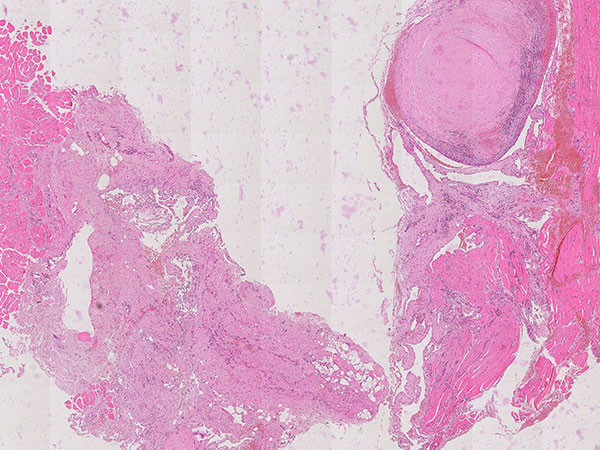

Hämatoxylin-Eosin-Färbung, 21-fache Vergrößerung: Rechts oben ein bereits bindegewebig umgewandelter Phlebolith dargestellt. Insgesamt als Hinweis auf eine gefäßartige Läsion vermehrt einige fuchsbauartige, irreguläre, gefäßartige Hohlräume sichtbar im histopathologischen Übersichtsbild.

Hämatoxylin-Eosin-Färbung, 64-fache Vergrößerung: Schichtartiger, vor allem zentral vorwiegend bindegewebiger Aufbau des bereits älteren, teilorganisierten Phlebolithen. Umgeben wird der Phlebolith von multiplen vermehrten, irregular aufgebauten, dünnwandigen Gefäßräumen.